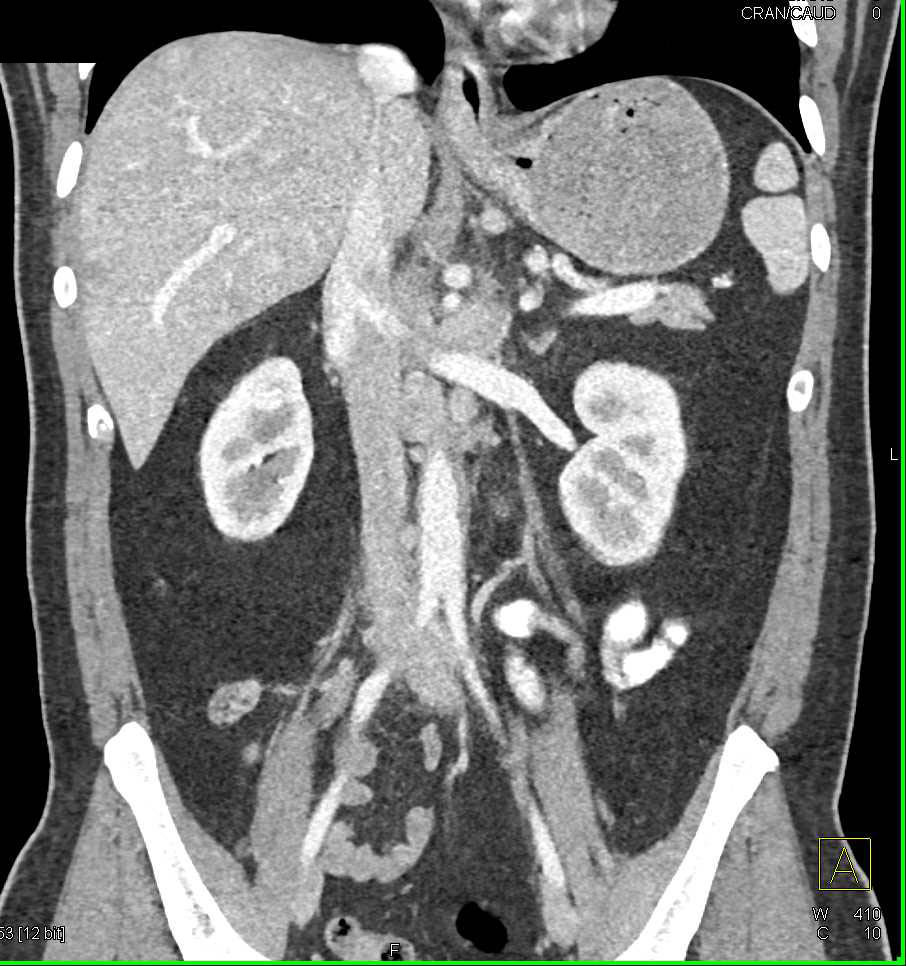

Diffuse Gastric Fold Thickening due to Zollinger-Ellison Syndrome